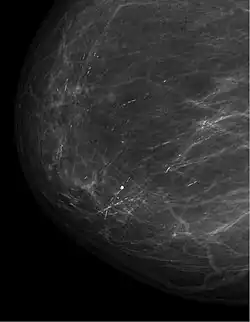

Differentialdiagnose und weitere Diagnostik

Wichtig ist, dass bei einer Mastitis non puerperalis ein Malignom nach Abheilung der Entzündung ausgeschlossen wird (Mammakarzinom, Paget-Karzinom, inflammatorisches Mammakarzinom).

Die periduktale Mastitis, auch plasmazelluläre bzw. granulomatöse Mastitis genannt, ist eine abakterielle und chronische Mastitis, die durch einen Sekretverhalt ausgelöst wird. Durch den Sekretverhalt kommt es zur Ektasie der Milchgänge mit übertreten des Sekretes in das umgebende Gewebe mit daraus resultierender Entzündungsreaktion. Betroffen sind vor allem Frauen mittleren Alters. Wichtig ist der Ausschluss eines Malignoms.